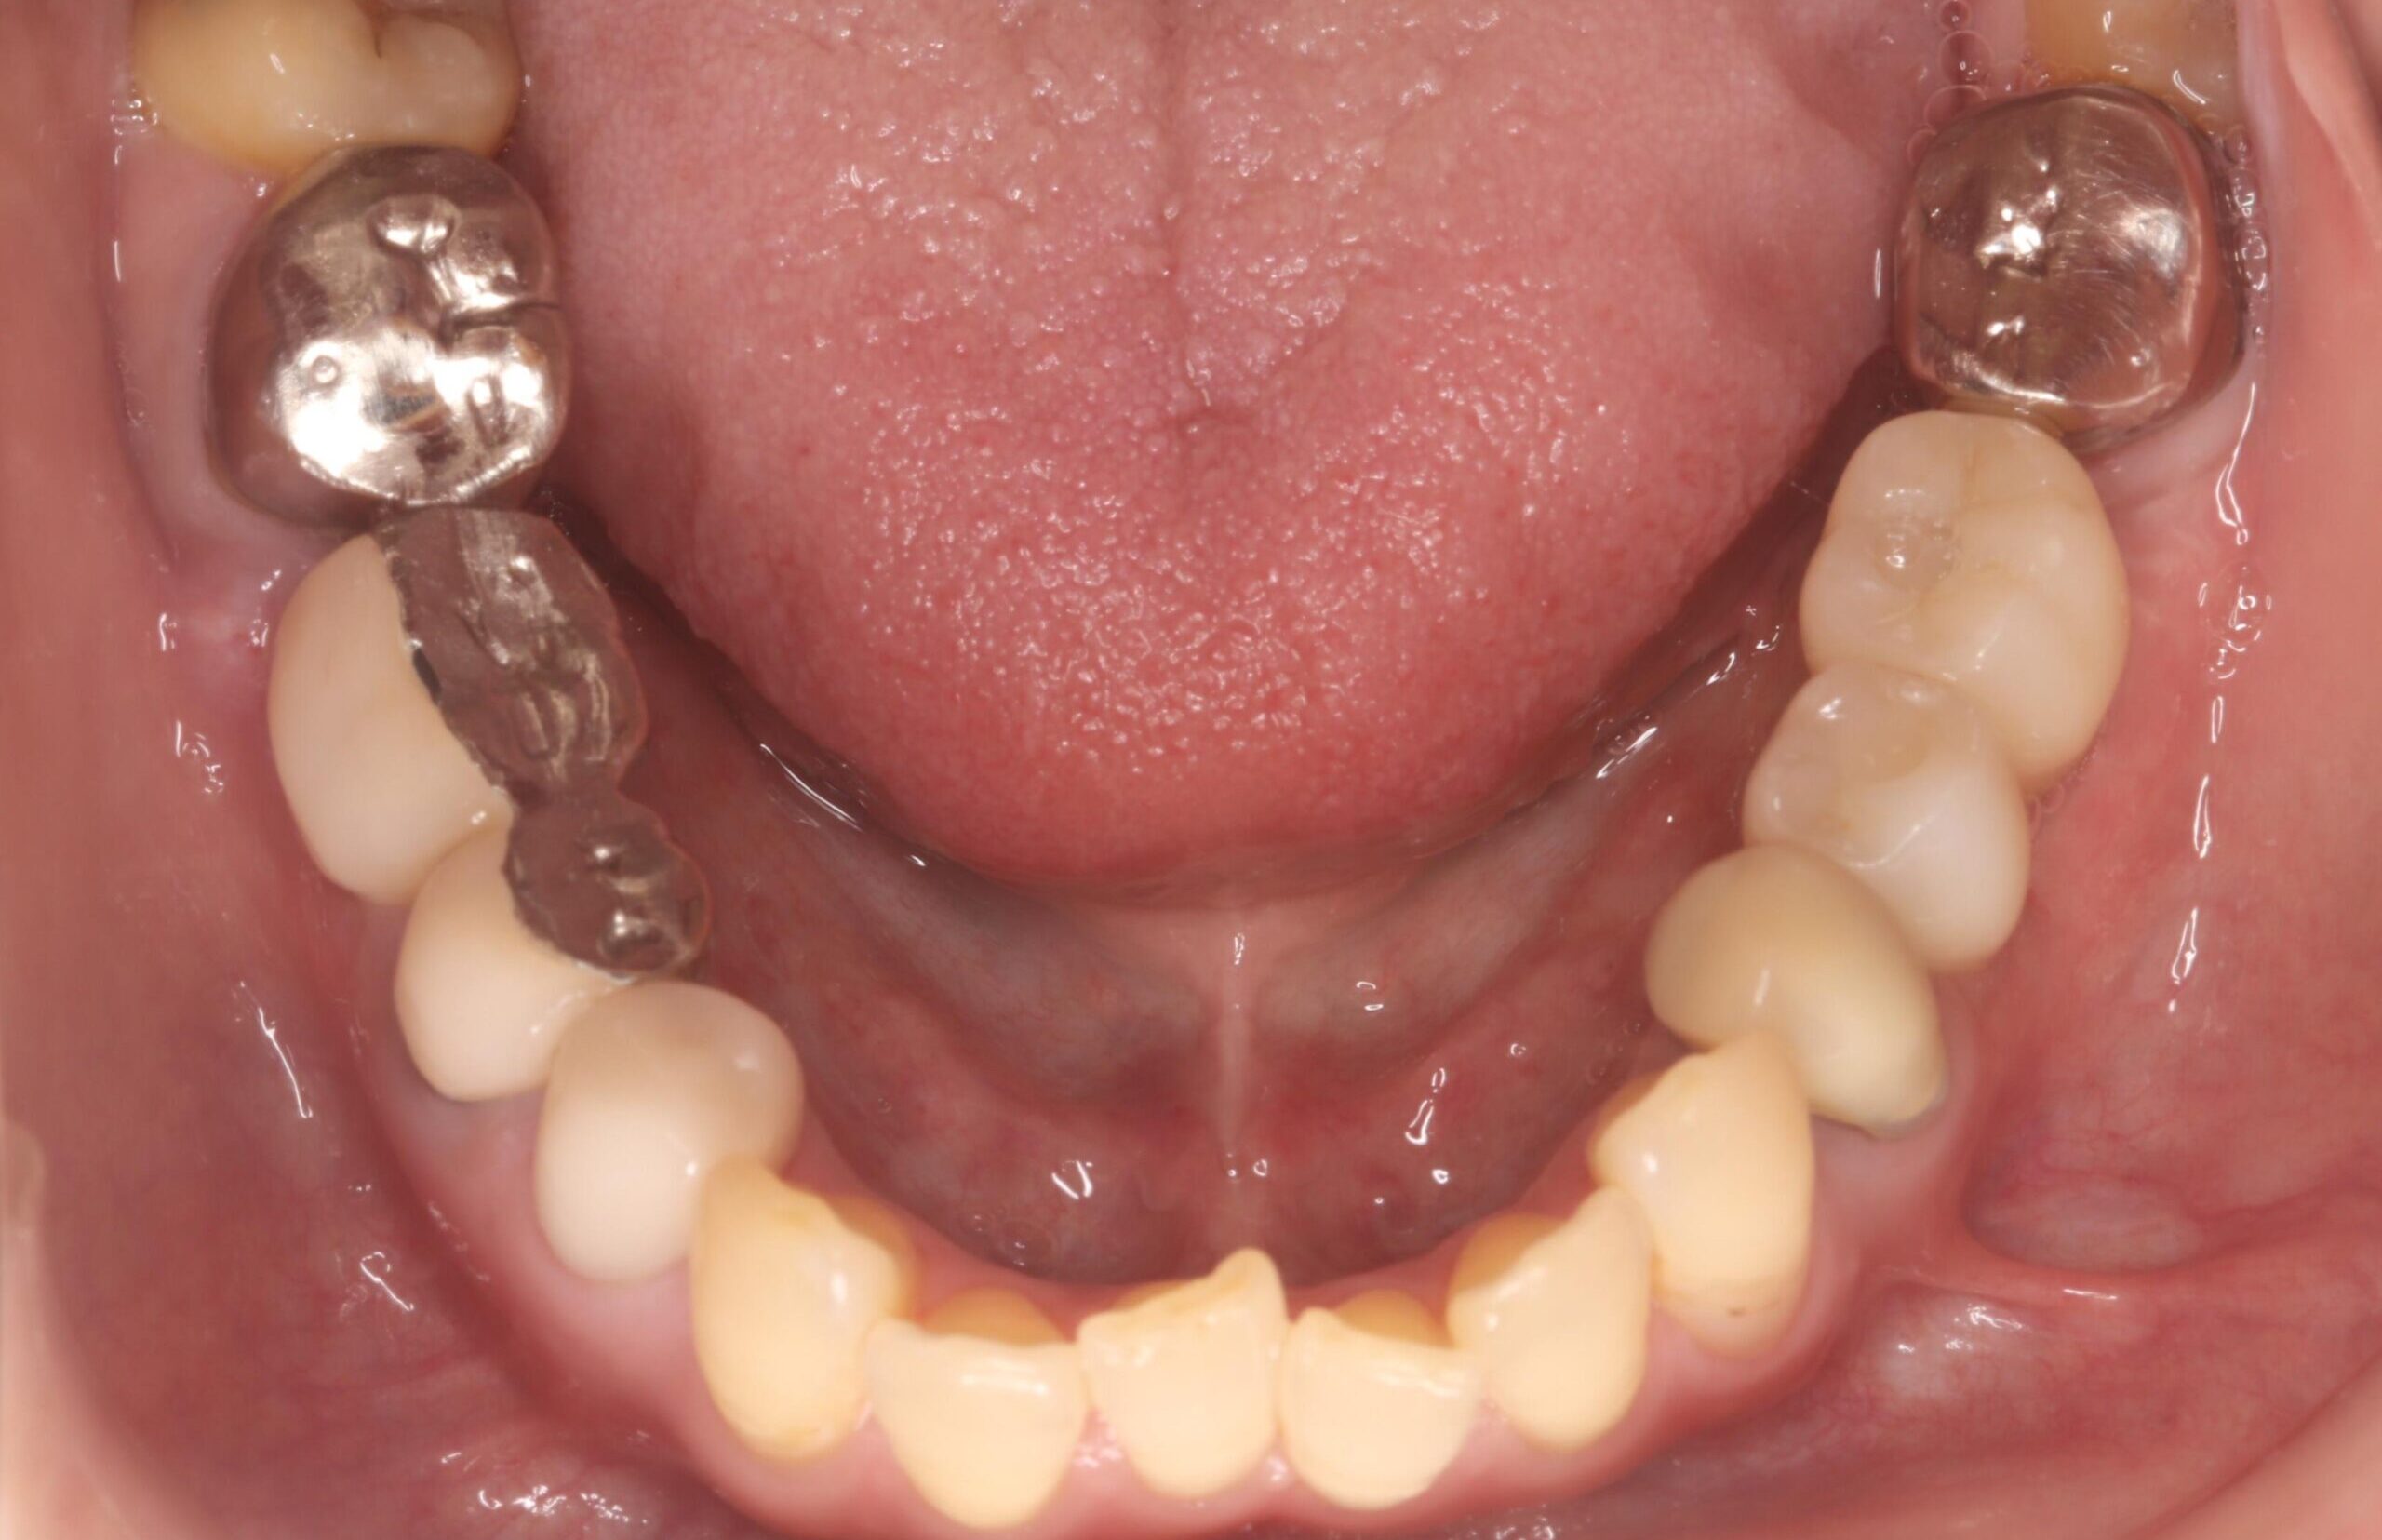

症例02

70代 男性 咬み合わせが強く多くの歯がすぐに壊れる

| 主訴 | 咬み合わせが強く、治療をしてもつくった歯がすぐに壊れる。 他院ではインプラントをいれることも難しいため、断られた。 |

|---|---|

| 年代・性別 | 70代 男性 |

| 治療部位 | 下顎両側 5,6 上顎右側 4 6のインプラントブリッジ ※全顎的に、臨床的歯冠長延長術(クラウンレングスニング)を行い、セラミッククラウンの強度を増しています。 |

| 治療費用 | インプラント 440,000円×6本 |

| 手術回数 | 下顎1回 上顎1回 |

| 治療期間 | 下顎6ヶ月 上顎6ヶ月 |

| 手術時間 | 下顎90分 上顎60分 |

| 治療回数 | 下顎1回 上顎1回 |